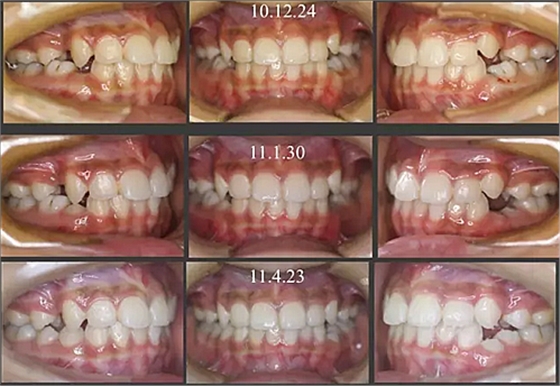

經(jīng)過三年零九個月的看護(hù),最終戴上了固定矯治器,但是大家不難發(fā)現(xiàn),孩子的牙齒已經(jīng)排齊,上下中線也基本對齊,面型也好看多了,這樣矯正就變得簡單,療程自然縮短,孩子也不遭罪了。

這個故事告訴我們,只有家長早點把孩子帶給正畸醫(yī)生檢查,才能早期發(fā)現(xiàn)早期治療。起到了事半功倍的效果。矯正以后還不容易復(fù)發(fā),因為從08年的初診到11年戴矯正器這三年多的時間里,孩子的牙齒是自己長好的。